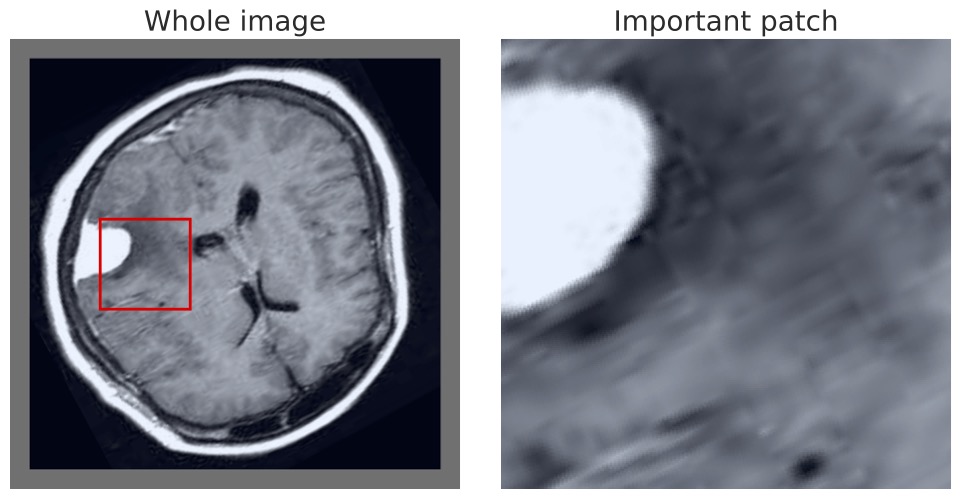

Finally, we can also visualize the results of our MIL model in the same manner as prior approaches, highlighting either the most positive, or all positive, regions to allow interpretable inspection and verification. This is demonstrated in Figure 6 using the BTMD dataset, in which tumors are recognizable to non-medical experts. The appendix has additional random samples from the other dataset.

In Figure 9 we show multiple BTMD images randomly selected and the maximal positive detection region from each image. In each case it is clear that the model successfully focuses on the malignant portions.

VSA-MIL further succeeds in detecting more than just the singular region of malignancy. This is confirmed by visualizing all overlapping sub-regions that are detected as positive malignancy, demonstrated in Figure 11. We make note that in some cases adjusting the size of the patch may yield more intuitive results depending on the size of what needs to be detected, but did not alter this to be aligned with prior articles and the patch size previous used.